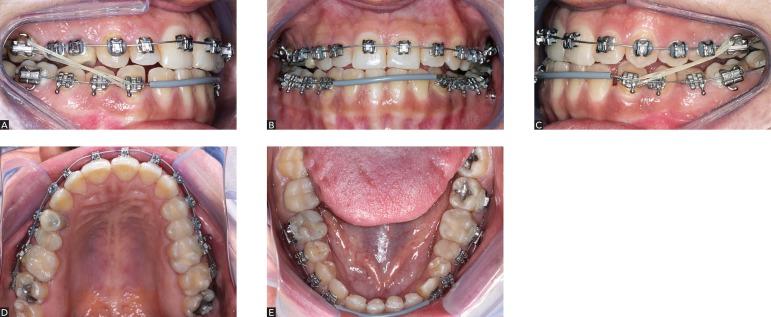

This paper aims at presenting a well-defined protocol employed to produce a better treatment performance during this period of technological transition. It explores the advantages of each system, particularly with regards to reduced treatment time and increased compensatory tooth movement in adult patients. It particularly addresses compensable Class III malocclusions, comparing the self-ligating brackets system, in which greater expansive and protrusive tooth movement (maxillary arch) is expected, with Capelozza Prescription III conventional brackets, in which maintaining the original form of the arch (mandibular arch) with as little changes as possible is key to yield the desired results.

本文旨在介绍一种明确的方案,用于在这一技术过渡时期实现更好的治疗效果。它探讨了每种系统的优势,特别是在缩短成年患者治疗时间和增加代偿性牙齿移动方面。它特别针对可代偿的III类错牙合畸形,比较自锁托槽系统(预期上颌弓有更大的扩弓和前突牙齿移动)与卡佩洛扎III型传统托槽(尽可能少地改变下颌弓的原始形态以获得理想效果的关键)。